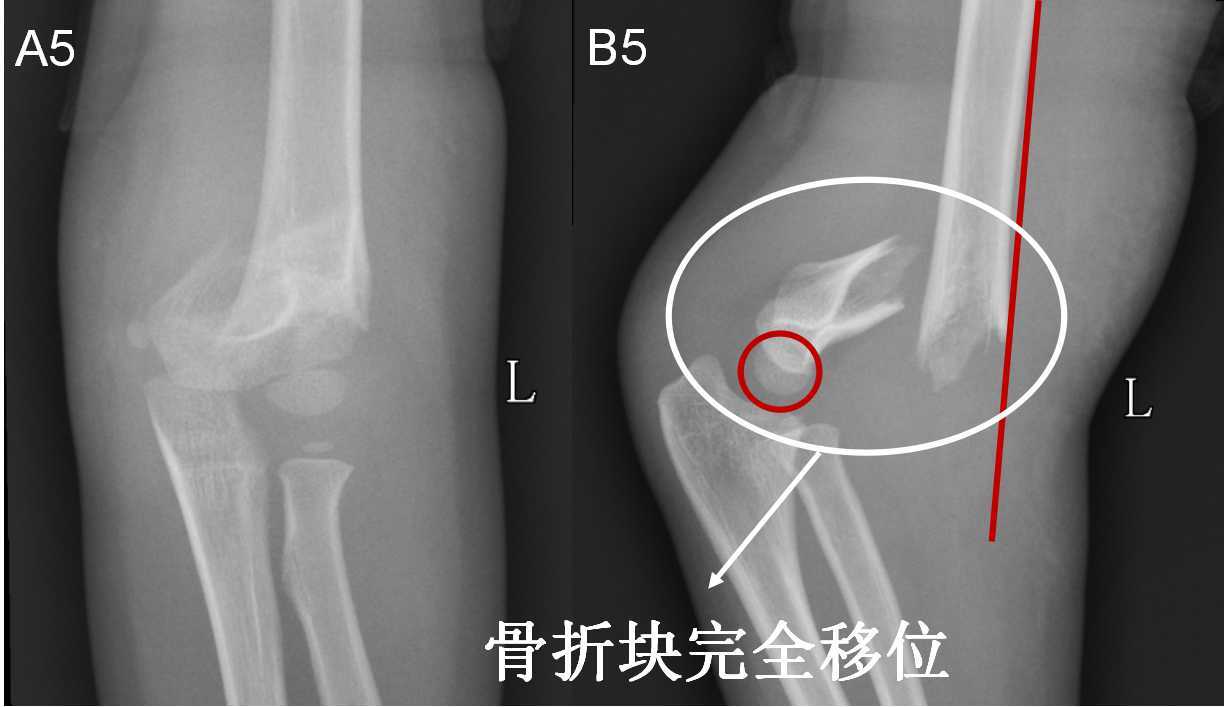

7种 肘部损伤x片详细图解 小头

一分钟让您明白肱骨髁上骨折什么时候要手术 什么时候不用手术 肱骨骨折 肱骨骨折

病例分享 常见儿童肘部骨折及治疗

儿童肘部损伤x线诊断涂占海 Ppt Download